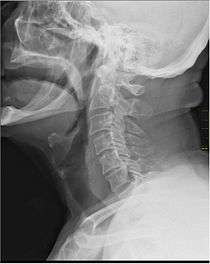

X-Ray showing the throat. Note the dark colored band anterior to the spine. | |

In vertebrate anatomy, the throat (Latin: gula) is the anterior part of the neck, positioned in front of the vertebra. It contains the pharynx and larynx. An important section of it is the epiglottis, which is a flap separating the esophagus from the trachea (windpipe) preventing food and drink being inhaled into the lungs.[1] The throat contains various blood vessels, pharyngeal muscles, the nasopharyngeal tonsil, the tonsils, the palatine uvula, the trachea, the esophagus, and the vocal cords.[2] Mammal throats consist of two bones, the hyoid bone and the clavicle. The "throat" is sometimes thought to be synonymous for the isthmus of the fauces.[3]